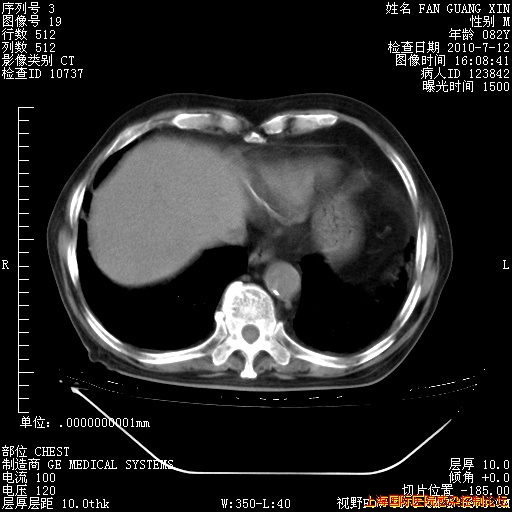

今天CT

整整相隔30天的肺部CT好像有所好转啊。甲强龙减量第3天,需要观察体温。

海管,自昨日你和我通完话后,不知您岳父消化道症状有无缓解?体温怎样?阅读7.12日胸部ct,个人认为目前激素治疗是有效的,甲强龙减量是适宜的。因在抗痨治疗,需密切观察肝功、肾功能和血常规。不过,老年、长期住院和大量使用激素,很担心菌群失调发生